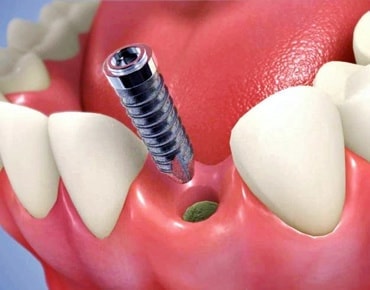

インプラントとは、顎の骨に人工歯根となる金属を埋め込み、その金属を土台にして、天然の歯と同じような人工の歯を取り付ける治療方法です。

埋め込む金属に生体との親和性が高いチタンが使われる事が多く、チタンは長年の臨床研究でインプラントの素材として最も安全であり、また顎の骨としっかり結合することが確認されています。

天然歯のような見栄えだけでなく、これまでの入れ歯やブリッジでは満足することが難しかった「食べる・話す」という機能も回復できます。

インプラントは周りの歯を傷つけず、残った歯への影響が少ないため、自分の歯を多く残せます。